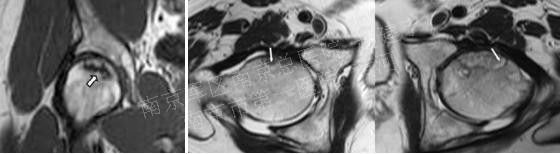

2.影像学检查: 髋部正位片及蛙式位片仍是重要的诊断手段,正位片最初的阳性表现为头下的硬化带及囊性改变,由于正位片中髋臼前后缘与股骨头上方存在重叠,有可能导致病损区显示不清,因此蛙式位片不可或缺,随着病情发展,软骨下骨与软骨分层,X片上则表现为新月征的特点;由于疾病早期X片可无阳性表现,MRI是目前诊断ONFH的“金标准”,其特征性体现在T1加权像上的低密度信号以及T2加权像的高密度信号,是坏死骨与活性骨的交界处出现大量富含血管的肉芽组织的表现。

T-1 W可见ONFH典型的“条带状”低信号,T-2 W可见双侧股骨头“双线征”表现,外层高信号而内层为低信号

X片无异常,但T-1 W可见典型的条带状低信号改变

平片中可见软骨下骨硬化,边缘不清;T-1 W则可清晰显示病损范围